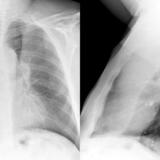

LUL Collapse Case 1 PA and Lateral

Date: 02/19/2004

Views: 3555